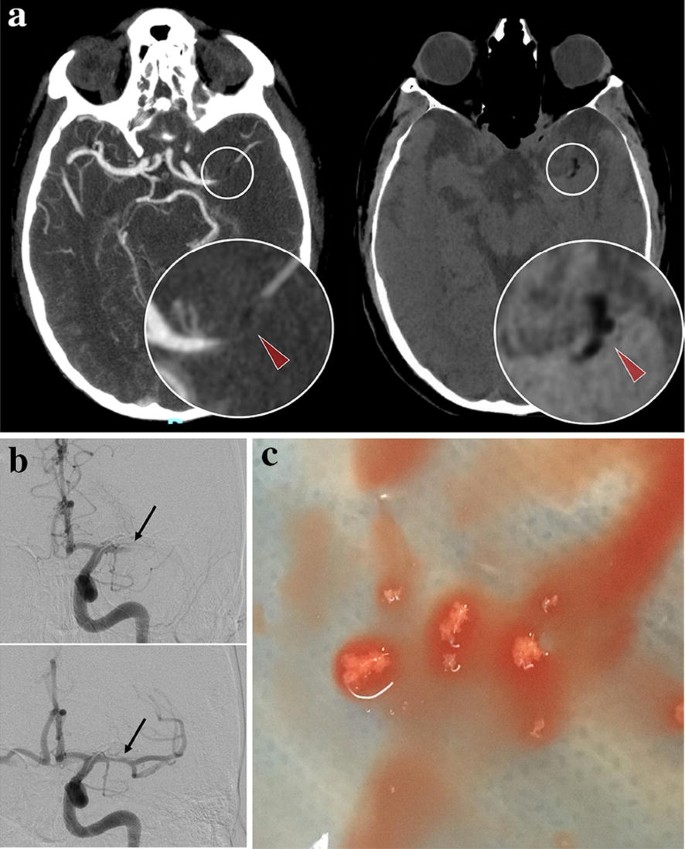

A 56-year-old patient underwent a right knee replacement under spinal anesthesia. At the end of the procedure, he suddenly developed right hemiplegia and aphasia. Emergent brain computed tomography (CT) revealed a left middle cerebral artery occlusion by material of negative density (− 33 Hounsfield Unit), highly suggestive of fat embolus (Fig. 1a). Indeed, this image differs from the typical hyperdense artery sign, which shows thrombus. Mechanical thrombectomy was successfully achieved by thrombo-aspiration (Fig. 1b) and retrieved spumous fat fragments (Fig. 1c). In this context of acute setting during orthopedic surgery, an intra-cardiac right-left shunt was searched during diagnostic work-up. Transesophageal echocardiography revealed a patent foramen ovale with an atrial septal aneurysm, supporting a paradoxical embolism of fat material released during surgery. The patient recovered well.

a Injected cerebral computed tomography demonstrating left middle cerebral artery occlusion (left panel) due to a negative density embolus (− 33 Hounsfield Units, red arrowheads). b Pre- and post-aspiration angiographic runs showing arterial occlusion (top, black arrow) and complete revascularization of the left middle cerebral artery (bottom, black arrow). c Macroscopic aspect of the fat embolus after thrombectomy by direct intracranial aspiration

Brain CT remains the standard for acute neurological disorders because of its almost universal availability, and speed of acquisition, especially in the context of stroke, where every minute counts. In some cases, brain CT may also provide a pathognomonic clue of embolus constitution and help tailor revascularization strategy, i.e., the use of direct aspiration instead of a stentriever for a deemed friable fat embolus in this case.